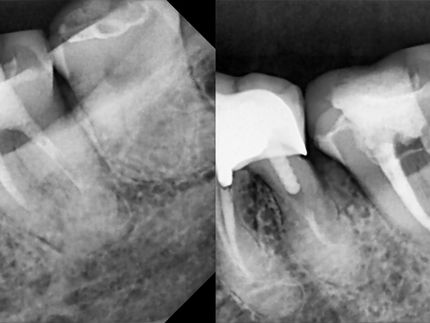

Endodontic treatment aims to repair and save a badly damaged infected tooth. the procedure involves removing the damaged pulp or nerve, cleaning disinfecting it, and then filling and sealing it.

The following cases were done using MTWO rotary endodontic instruments by VDW for fast and safe root canal preparation.